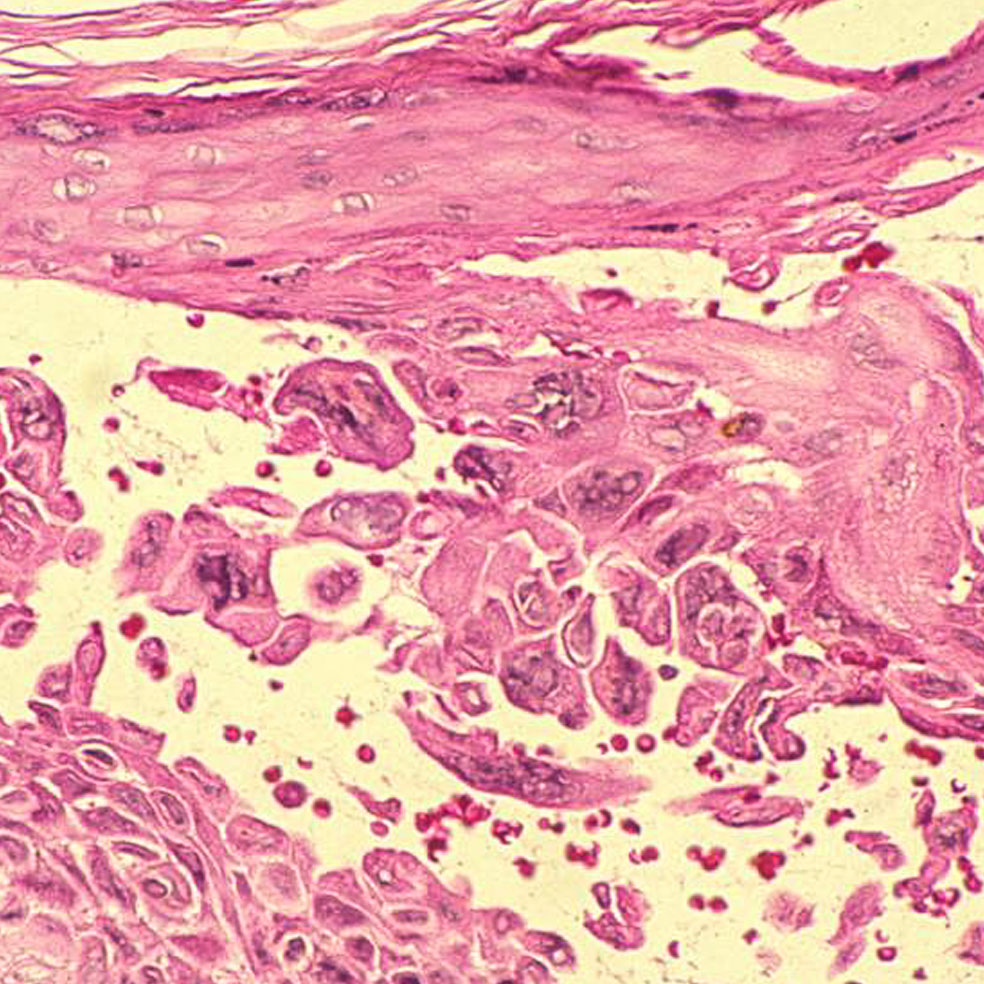

El origen se halla en tres tipos de hongos: Microsporum, Epidermophyton y Trichophyton, criaturas milenarias que invaden las capas superficiales de la piel, el pelo y las uñas. Es donde encuentran alimento y se reproducen. Por eso una vez ahí se multiplican, generando una erupción cutánea redondeada que se deshace en escamas y causa picor. Si no se trata a tiempo, puede provocar dolor, fiebre, caída del cabello e, incluso, alopecia en las zonas afectadas. Su capacidad de transmisión es muy elevada: basta tocar a una persona infectada u objetos contaminados como las máquinas en cuestión, peines, ropa, suelo de duchas, piscinas...

Trichophyton y Epidermophyton son dos géneros de hongos que se pegan a los pies en las duchas públicas, ocasionando una infección conocida como tiña podal o pie de atleta. Estos microorganismos proliferan en zonas cálidas y húmedas, por lo que se recomienda tener los pies limpios y secos, sobre todo entre los dedos.